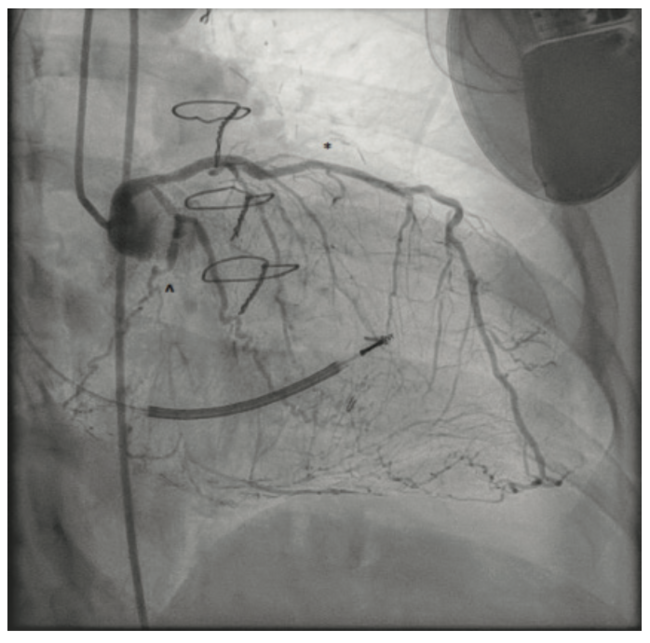

Her right radial artery was known to be occluded from prior catheterizations and her left radial was used in her CABG previously; thus, cardiac catheterization was performed from the right femoral artery. Coronary angiography demonstrated (Figure 2) patent stents in the left anterior descending (LAD) and the complex lesion in the left circumflex (LCx) distal to the first obtuse marginal (OM1). The distal LCx supplied several posterolateral branches and filled via bridging and other ipsilateral collaterals. Interestingly, the remains of a free radial jump graft from the distal LCx also supplied the right posterior descending artery (RPDA) (Figure 3). The right coronary artery (RCA) was not engaged and was known to have a complex lesion in the proximal segment.

The ipsilateral collaterals to the culprit vessel precluded the need for dual access, and a 6 French (F) VL3 guide catheter (Boston Scientific) was placed via the right femoral access. A Turnpike LP microcatheter (Teleflex) was used for wire support and exchanges. Initial crossing attempts with Runthrough NS Extra Floppy (Terumo Interventional Systems) and Fielder XT-a (Asahi Intecc) wires were unsuccessful. The lesion was crossed successfully with a MiracleBros 6 (Asahi Intecc) wire and the tip was clearly visualized in the remains of the jump graft (Figure 4). Attempts to then cross the lesion with Turnpike LP and Turnpike Gold microcatheters (Teleflex) for lesion dilation and possible wire exchange were unsuccessful despite very good guide support (Figure 5).